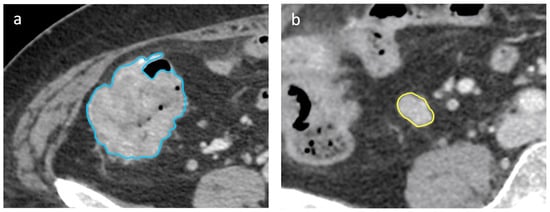

2.4. CT Scan Segmentation Analysis

2.5. Radiomic Features Extraction

3.3. D Segmentation and LN’s Radiomic Features

3.4. Lymph Node/Primary Lesion (LN/PL) Ratio